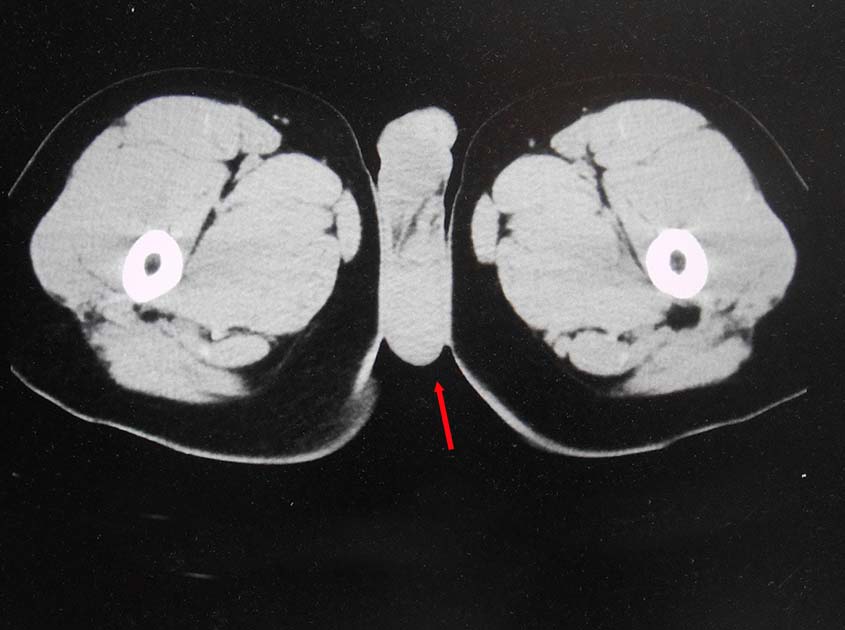

無痛性精巣腫大で泌尿器科受診. 画像診断では, 左精巣最大径4.5cmの腫瘤で縦隔リンパ節転移が疑われた. 左高位精巣摘除術をうける.

画像: 左精巣腫瘤. 縦隔リンパ節転移疑い.